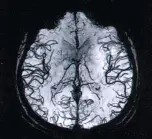

ПРИМЕРЫ ИЗОБРАЖЕНИЙ, сделанных на нашем оборудовании.

Исследование головного, спинного мозга и сосудов. Уникальные возможности оборудования позволяют визуализировать сосуды головного мозга и с высочайшей степенью достоверности, диагностировать сосудистую патологию головного мозга, включая сосудистые программы для оценки состояния мелких сосудов.